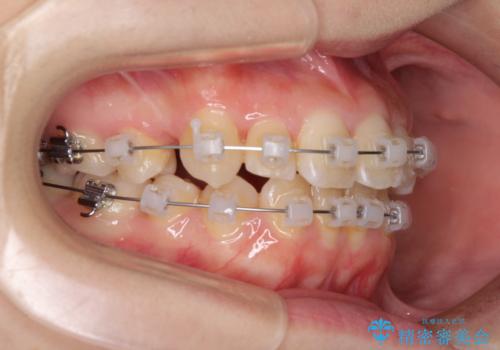

- 矯正装置

- クリアブラケット

- 治療期間

- 2年2ヶ月